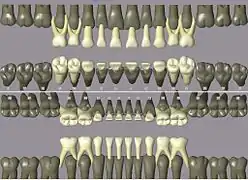

Codes, names, and usual number of roots: (see chart of teeth at Universal Numbering System)

- 11 21 51 61 maxillary central incisor 1

- 41 31 81 71 mandibular central incisor 1

- 12 22 52 62 maxillary lateral incisor 1

- 42 32 82 72 mandibular lateral incisor 1

- 13 23 53 63 maxillary canine 1

- 43 33 83 73 mandibular canine 1

- 14 24 maxillary first premolar 2

- 44 34 mandibular first premolar 1

- 15 25 maxillary second premolar 1

- 45 35 mandibular second premolar 1

- 16 26 54 64 maxillary first molar 3

- 46 36 84 74 mandibular first molar 2

- 17 27 55 65 maxillary second molar 3

- 47 37 85 75 mandibular second molar 2

- 18 28 maxillary third molar 3

- 48 38 mandibular third molar 2